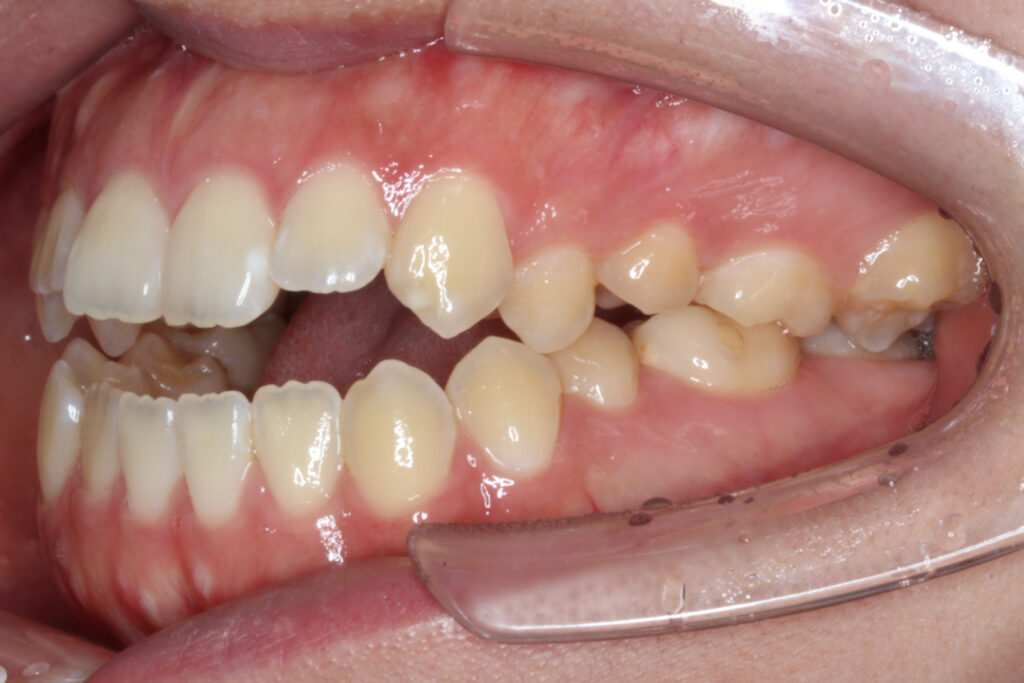

After

インビザラインは臼歯を「圧下」させることによって前歯を伸び出させずに開咬を治せるため、開咬に適した装置と言えます。

治療後は前歯もしっかりと噛み合うことで、機能的な歯並びを獲得することができました。